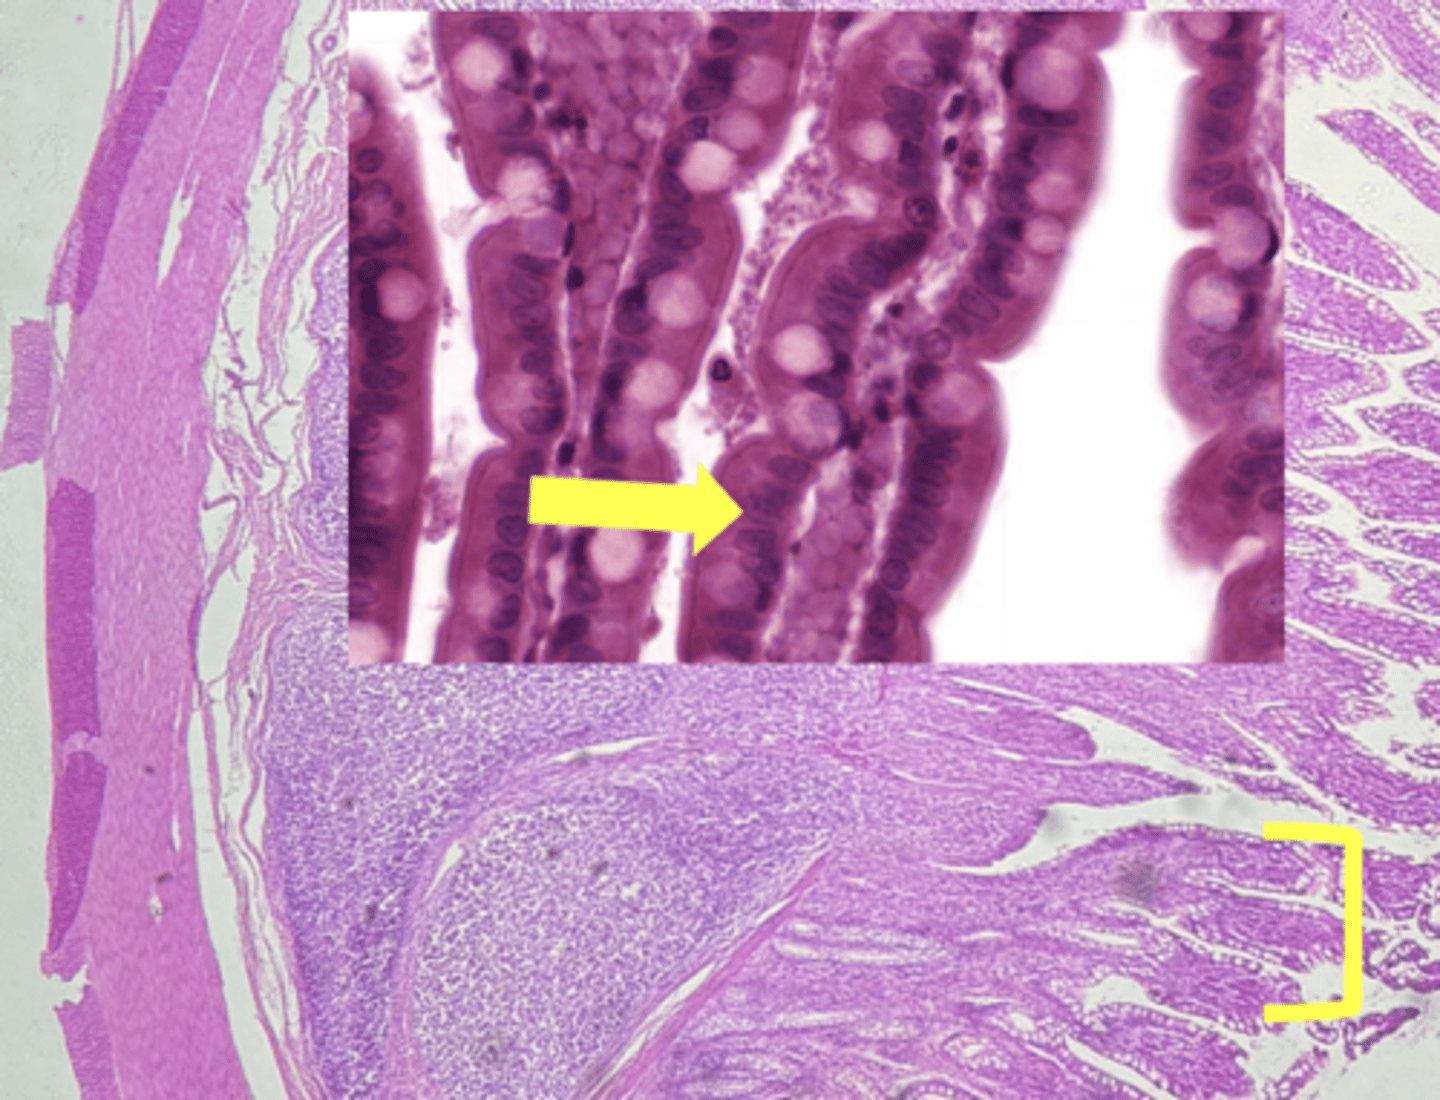

ileum-small intestine

type of tissue

payers patch (KEY CHARACTERISTIC)

(ilium)

villi

(ileum)

simple columnar epithelium

type of cell

goblet cell- mucous (KEY CHARACTERISTIC)

(ileum-increased # seen here)

type of cell & what it secretes

intestinal crypts

lamina propria

muscularis mucosae